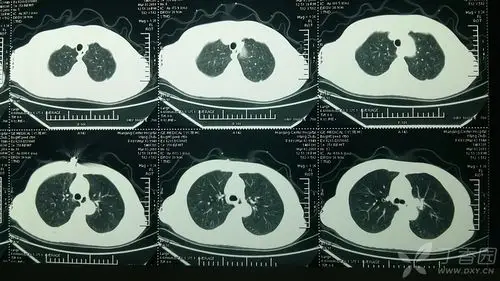

请问这个69岁女性ct扫描结果肺癌风险多大?